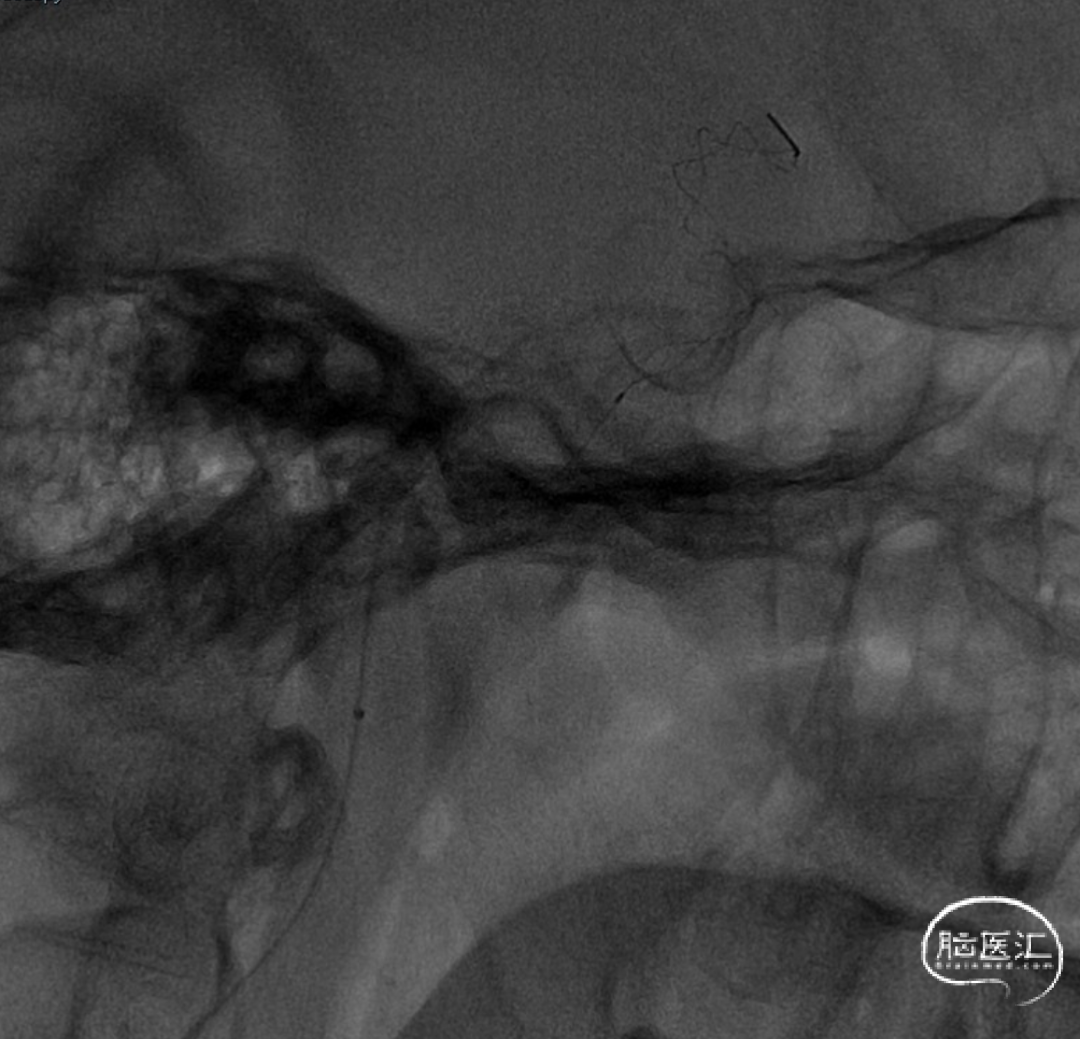

沿微导管送入4.0×30mm Syphonet®取栓支架,于M1-C7段释放作为栓塞保护装置。

沿4.0×30mm Syphonet®取栓支架输送导丝送入3.0×12mm SacSpeed®球囊扩张导管,自C1-C7段分次扩张,每次释压后跟进中间导管至C5段,复查造影显示血流通畅。

造影提示C5-C6段仍有残余狭窄。于是利用SacSpeed®球囊扩张导管收回部分Syphonet®取栓支架,在狭窄处直接扩张。

撤回SacSpeed®球囊扩张导管,复查造影。